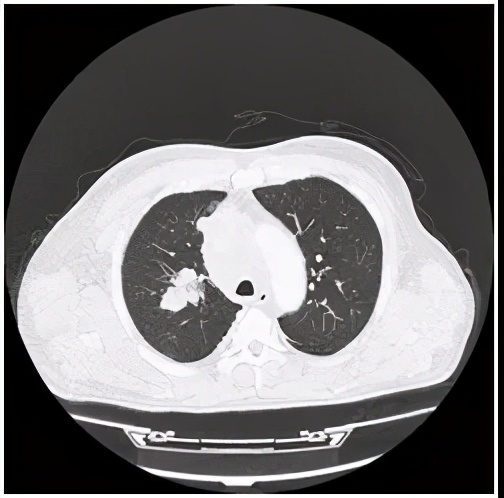

右肺肿瘤图